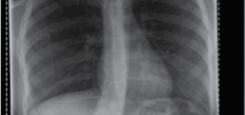

Clinical & Radiographic Imaging Archive